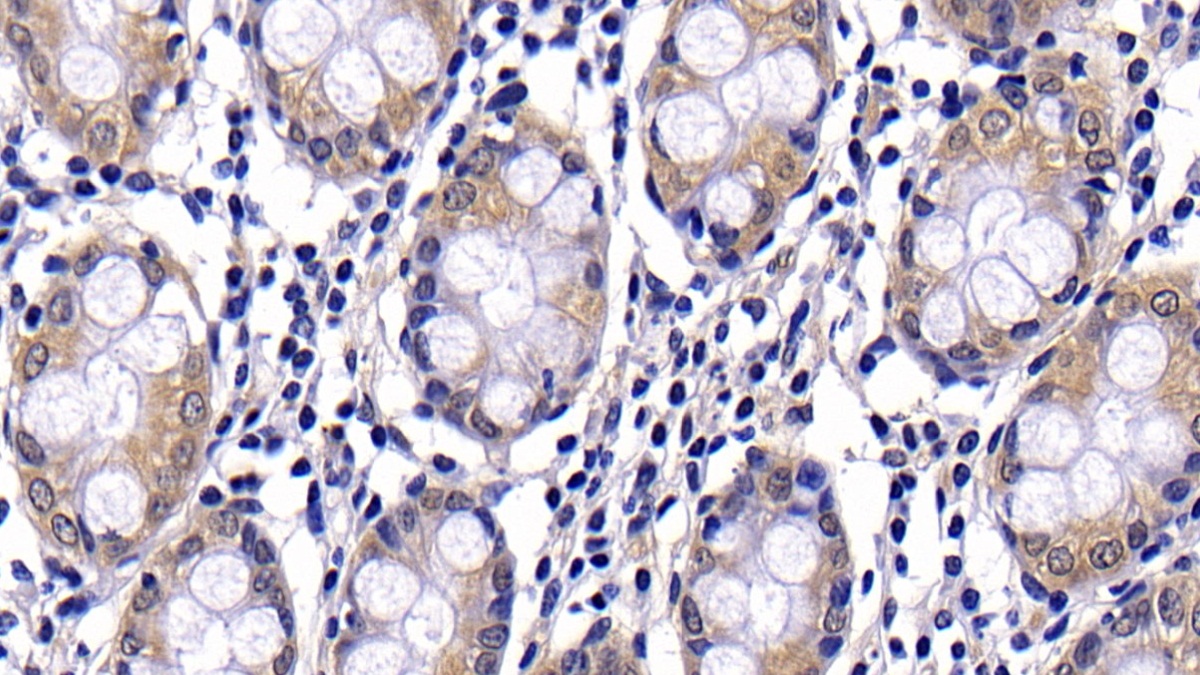

| Валидировано для | IHC WB Иммуногистохимия; Вестерн-блоттинг |

| Рекомендуемые разведения | WB: 0.2-3 мкг/мл; IHC: 2-30 мкг/мл; ICC: 2-30 мкг/мл; Оптимальное разведение определяется конечным потребителем |